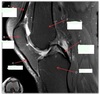

7

Q

What is letter A?

A

SUBSCAPULARIS MUSCLE

8

What is letter B?

10

What is letter D?

GLENOID

11

ANTERIOR LABRUM

How well did you know this?

1

Not at all

2

3

4

5

Perfectly

12